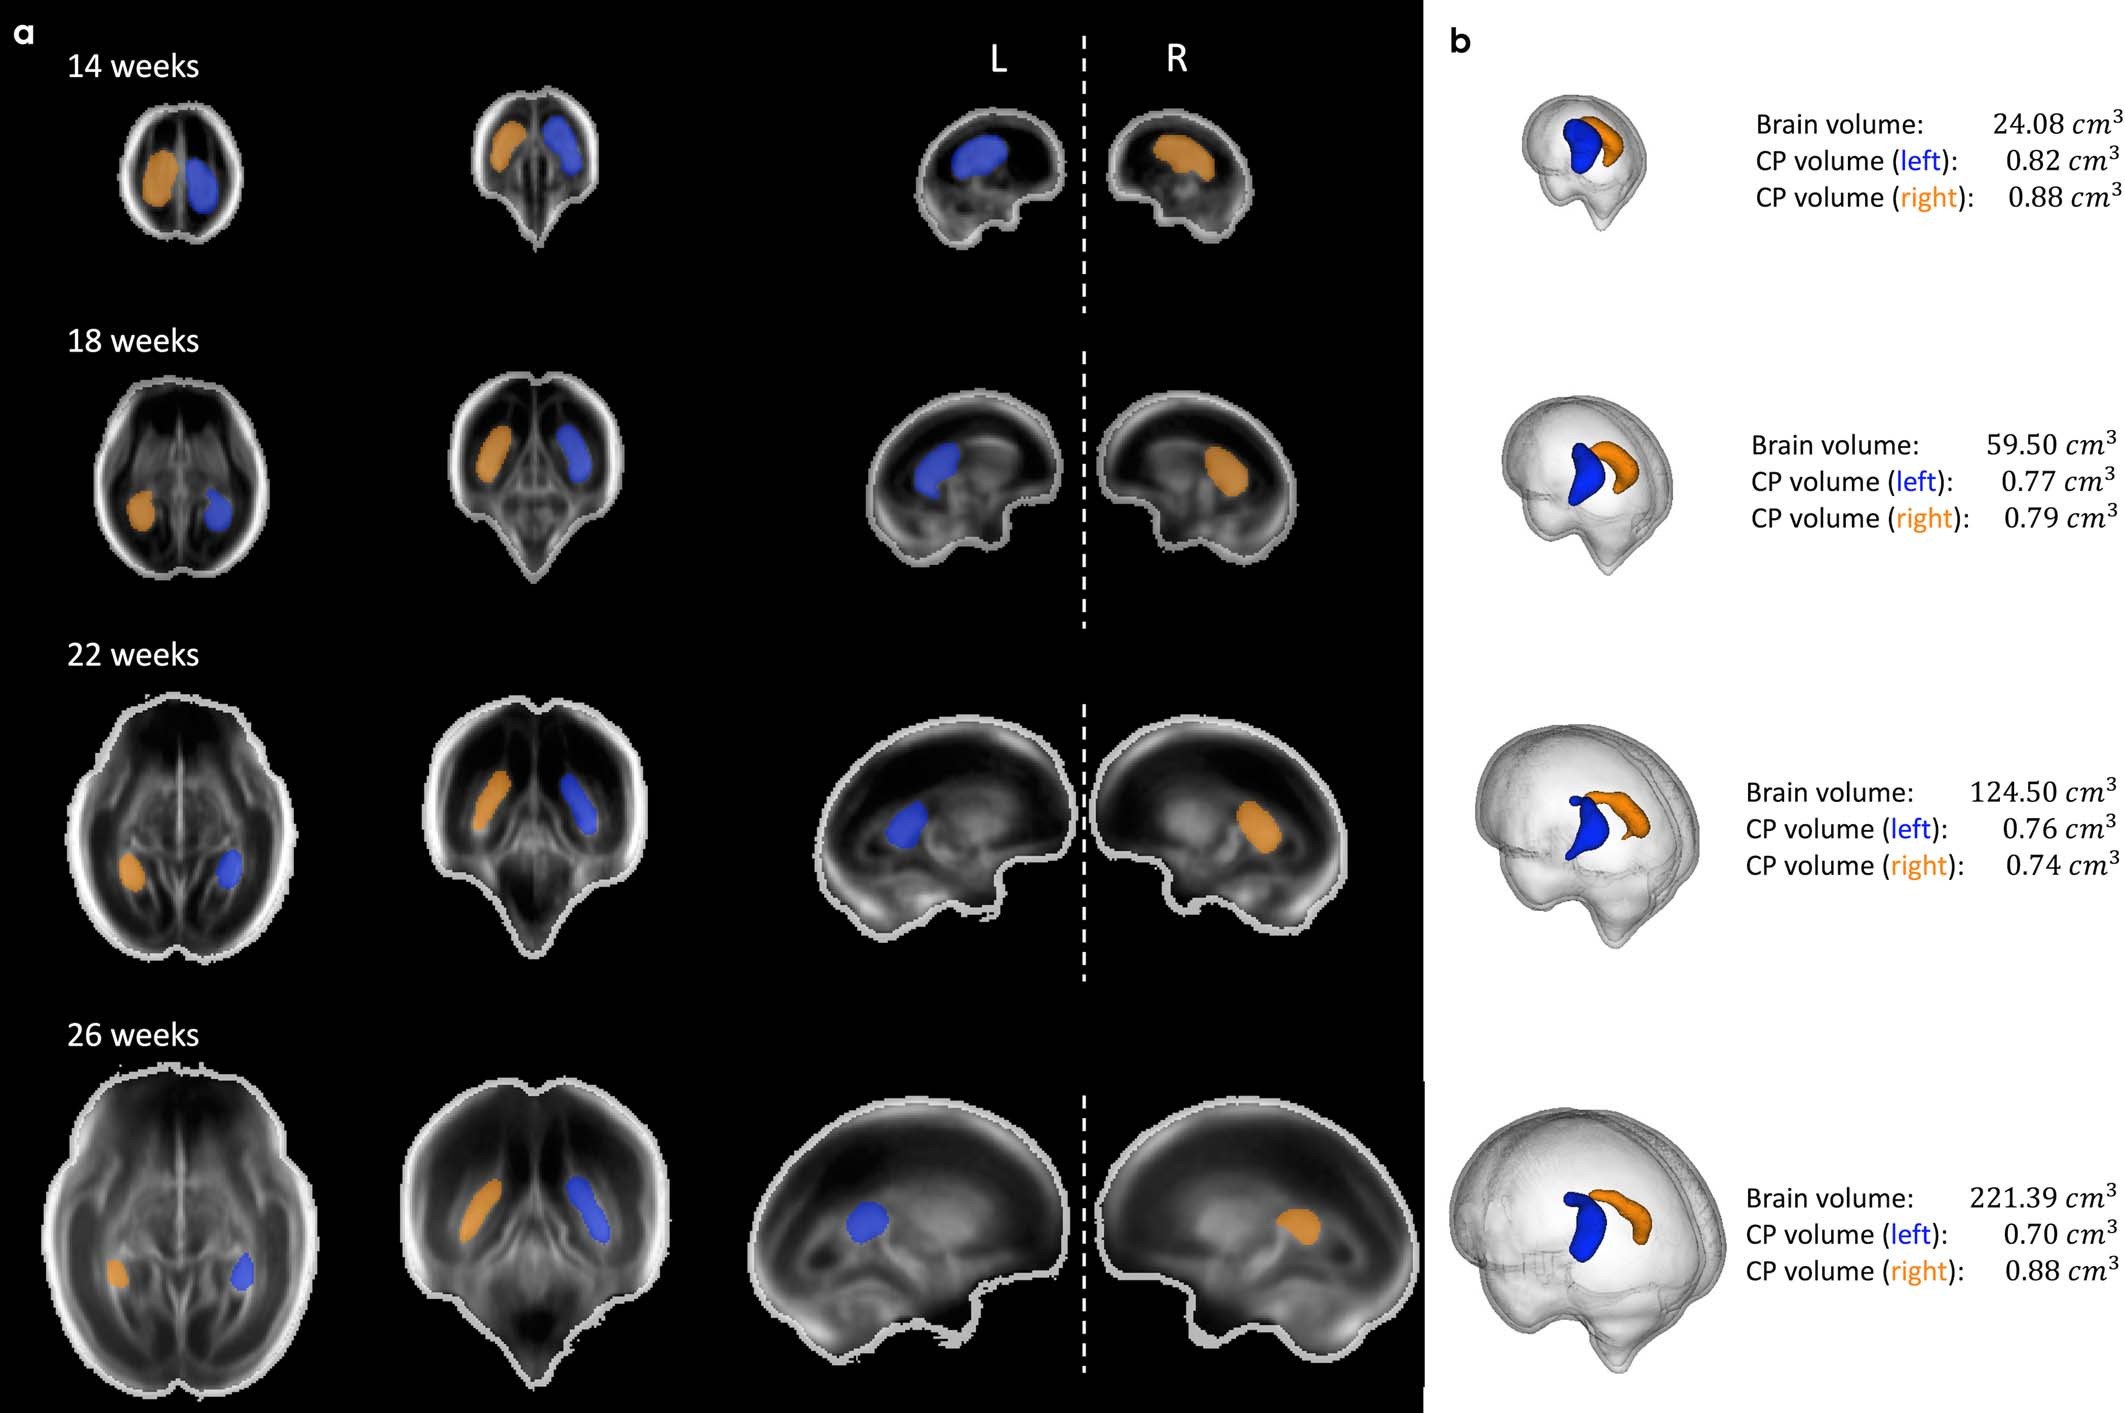

Extended Data Fig. 6: Choroid plexus asymmetry.

Mean total brain volume, left and right choroid plexus volumes derived from the fetal brain atlas at four gestational timepoints. (a) Axial (left column), coronal (middle), and sagittal (right) views shown, overlayed with segmentation maps of the choroid plexus (left hemisphere shown in blue; right shown in yellow). (b) 3D rendering of choroid plexus segmentations, relative to total brain volume.